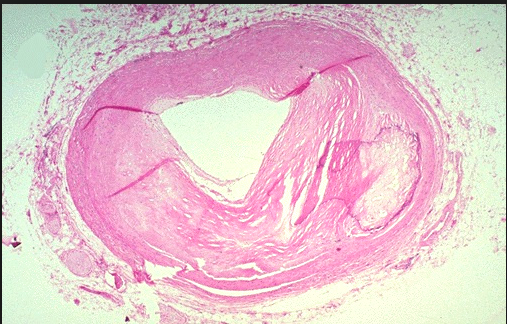

What is Fibromuscular dysplasia?

A developmental defect of the blood vessel wall, resuting in irregular thickening of large and medium sized arteries, especially the renal artery